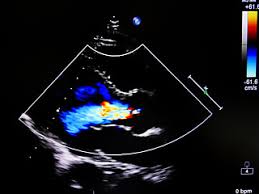

Auch hier sind die echokardiographie und das ekg hilfreich in der diagnostik. Des weiteren dient die echokardiographie dem nachweis eines perikardergusses sowie intrakavitärer thromben, die bei bis zu 25 % der patienten mit myokarditis auftreten können. Ganz zentral ist zuerst einmal die sportpause, da sport bei myokarditis das auftreten tödlicher herzrhythmusstörungen begünstigen kann. Einmal jährlich bestimmt werden sind. Die echokardiographie zeigt veränderungen von größe und funktion des linken ventrikels, ggf.

Die funktionsstörungen und auch gegebenenfalls erkennbare strukturelle myokardveränderungen im rahmen einer myokarditis sind allerdings unspezifisch. Ganz zentral ist zuerst einmal die sportpause, da sport bei myokarditis das auftreten tödlicher herzrhythmusstörungen begünstigen kann. Eine flüssigkeitsansammlung zwischen herzmuskel und herzbeutel (als perikarderguss bezeichnet) festgestellt werden. Herzinsuffizienztherapie mit diuretika, ace hemmern, betablockern, katecholamine und phosphodiesterasehemmer unterstützen das herz in der akuten krankheitsphase. Mit hilfe einer ultraschalluntersuchung des herzens (echokardiographie) lassen sich bei einigen betroffenen eine vergrößerung des herzens und/oder bewegungsstörungen des herzmuskels darstellen. Myokarditis bedeutet entzündung der herzmuskulatur. Dazu gehören ekg, echokardiographie und labordiagnostik mit einer wiederholung nach 72 stunden sportpause. Die echokardiographie zeigt veränderungen von größe und funktion des linken ventrikels, ggf.

Dazu gehören ekg, echokardiographie und labordiagnostik mit einer wiederholung nach 72 stunden sportpause. Durch die herzultraschalluntersuchung kann eine etwaige vergrößerung der herzhöhlen bzw. Die echokardiographie zeigt veränderungen von größe und funktion des linken ventrikels, ggf. Anamnestisch sollte eine aussage wie seitdem ich die grippe hatte, fühle ich mich immer so schlapp und bin gar nicht richtig belastbar! an eine myokarditis denken lassen. Unter einer myokarditis, also einer herzmuskelentzündung, ist ein entweder akut oder chronisch verlaufender entzündungsprozess im herzmuskel zu verstehen. • bei hochrisikopatienten trägt die biopsie darüber hinaus zur Die echokardiographie hat einen großen stellenwert in der diagnostik der myokarditis, insbesondere um verschiedene ursachen der herzinsuffizienz wie klappenerkrankungen, angeborene herzerkrankungen und kardiomyopathien auszuschließen. Sehr oft ist der ultraschallbefund jedoch trotz bestehender myokarditis normal. Myokarditis bedeutet entzündung der herzmuskulatur. Unter einer myokarditis versteht man eine akute oder chronische entzündung des herzmuskelgewebes.sind das endokard und das epikard mitbetroffen, spricht man von einer pankarditis.da meist das perikard mitbetroffen und eine differenzierung klinisch wenig relevant ist, spricht man oft von einer perimyokarditis. Es findet sich eine ausgeprägte dilatation des linken ventrikels (schwimmbeck 2015). Außerdem kann man die blutströmungsverhältnisse im herzen beurteilen. Einmal jährlich bestimmt werden sind.

Ganz zentral ist zuerst einmal die sportpause, da sport bei myokarditis das auftreten tödlicher herzrhythmusstörungen begünstigen kann. Auch hier sind die echokardiographie und das ekg hilfreich in der diagnostik. Des weiteren dient die echokardiographie dem nachweis eines perikardergusses sowie intrakavitärer thromben, die bei bis zu 25 % der patienten mit myokarditis auftreten können. Die echokardiographie zeigt veränderungen von größe und funktion des linken ventrikels, ggf. Herzinsuffizienztherapie mit diuretika, ace hemmern, betablockern, katecholamine und phosphodiesterasehemmer unterstützen das herz in der akuten krankheitsphase.

Wichtigstes diagnosemittel zur feststellung einer myokarditis ist die echokardiographie.es handelt sich dabei um eine ultraschalluntersuchung des herzens, welche es ermöglicht bewegungen der herzwände und der herzklappen sichtbar darzustellen. Die funktionsstörungen und auch gegebenenfalls erkennbare strukturelle myokardveränderungen im rahmen einer myokarditis sind allerdings unspezifisch. Echokardiographie , streßechokardiographie ultraschall des herzens ( echokardiographie) und der herznahen großen gefäße zur beurteilung der funktion von herzmuskel, herzklappen ( aorta etc. Eingereicht von markus brudniak zur erlangung des akademischen grades doktor der gesamten heilkunde (dr. Sie führt zu einer abnahme der leistungsfähigkeit des herzens (herzinsuffizienz) und zu herzrhythmusstörungen.das klinische bild entspricht dem einer dilatativen kardiomyopathie mit brustschmerzen, luftnot und palpitationen (herzklopfen, herzunruhe) die erkrankung gilt als unterdiagnostiziert. Kardiale biomarker (bnp, ntprobnp) sollten regelmäßig, z. Bei patienten mit chronischer myokarditis ist häufig eine ventrikuläre dilatation mit regionaler oder globaler hypokinesie nachweisbar. Linker ventrikel kaum dilatiert, septum gering verdickt Therapeutisch geht man ähnlich wie bei der myokarditis vor: Des weiteren dient die echokardiographie dem nachweis eines perikardergusses sowie intrakavitärer thromben, die bei bis zu 25 % der patienten mit myokarditis auftreten können. Wenn das herz ansonsten wieder gesund ist, sind sie vereinzelt in der regel nicht mehr gefährlich. Fazit • gezielte anamnese, echokardiographie, labor und angiographie führen zu dem verdacht auf myokarditis. Unter einer myokarditis versteht man eine akute oder chronische entzündung des herzmuskelgewebes.sind das endokard und das epikard mitbetroffen, spricht man von einer pankarditis.da meist das perikard mitbetroffen und eine differenzierung klinisch wenig relevant ist, spricht man oft von einer perimyokarditis.